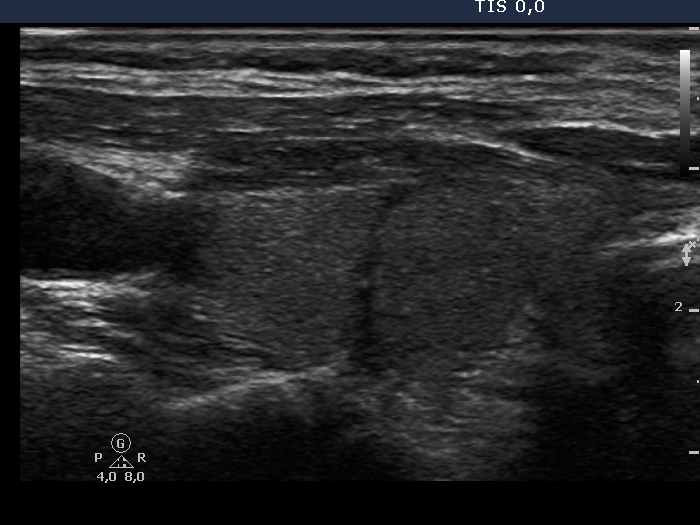

Clinical data: A 47-year-old woman underwent bilateral subtotal lobectomy for nodular goiter 6 years earlier. She was referred for regular follow-up examinations.

Ultrasonography. The thyroid was composed of circumscribed echonormal and minimally hypoechogenic areas divided by fibrous tissue. None of these areas corresponded to a nodule in a pathological sense.